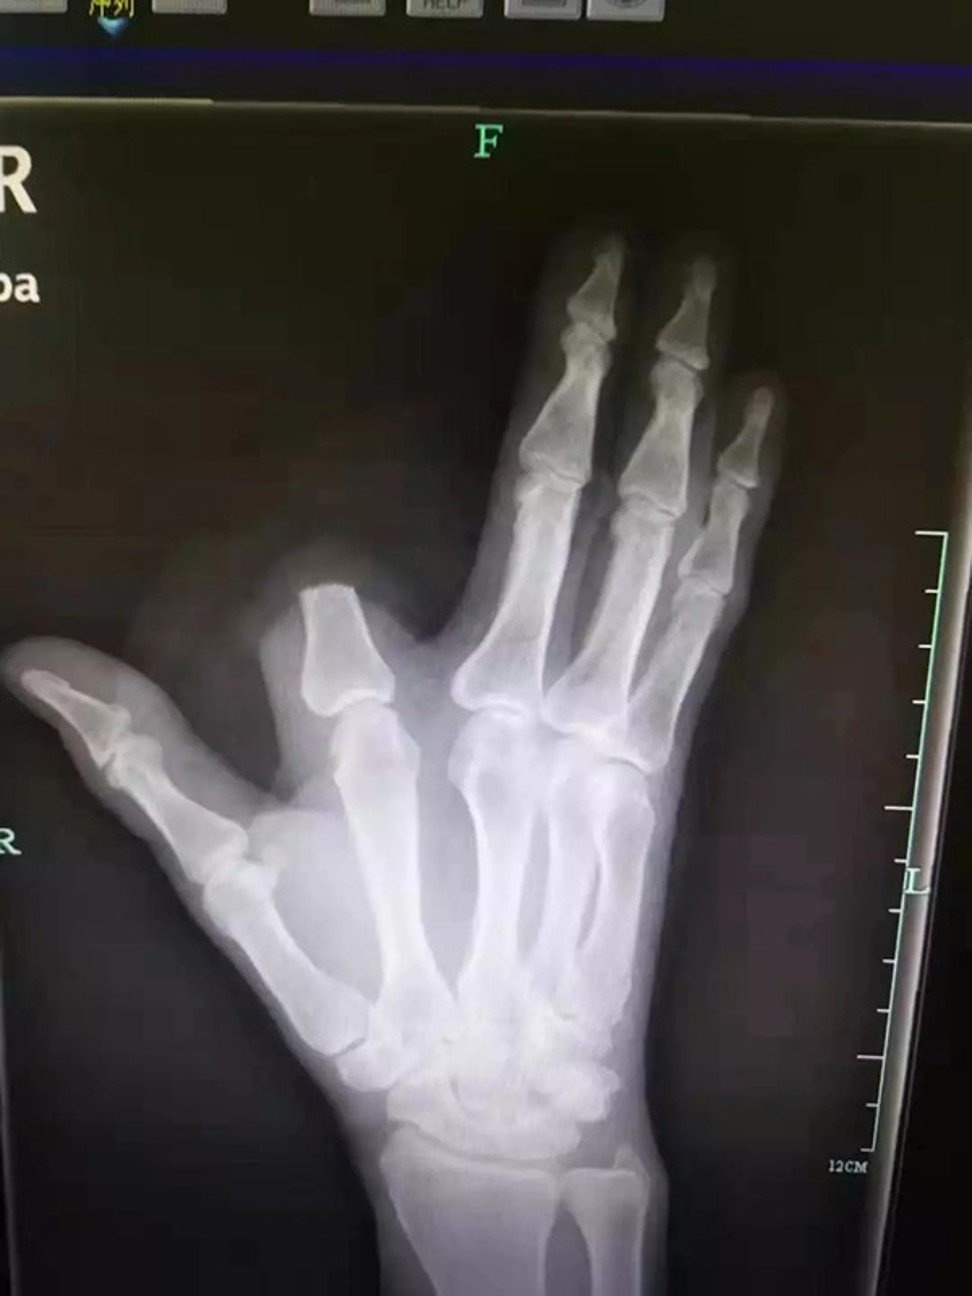

Tuy nhiên, ông đã để lại ngón tay bị chặt đứt lìa ở lại hiện trường, thế nên các bác sĩ không thể tiến hành ghép nối lại cho ông.

| Các bác sĩ đã không thể nối lại ngón tay cho nạn nhân. Ảnh: Weibo. |